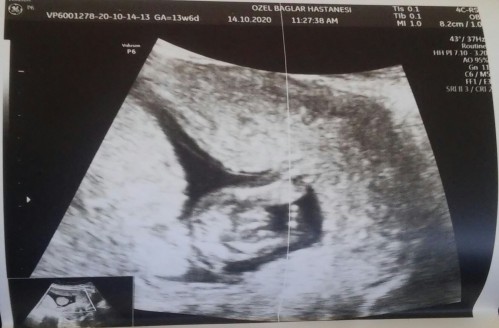

2. Fotoğraf..........

Bacak arası bu görüntü değil mi canım.

Malesef bilemedin bacak arasi atmışim zoomlu pipi resmi

Sanki iki dudağı var gibi . Kız sanirsam

Bence erkek çıkıntı var çünkü kiz da bu kadar olmuyor dünde ben ogrendim aynı böyleydi :)